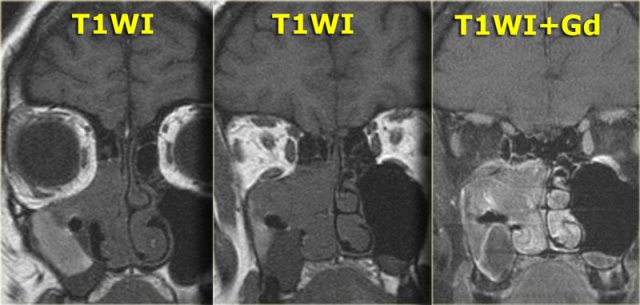

On the left images of a 64-yrs-old, immuno-competent patient, who had a follow-up scan for left-sided vestibular neuroma.

On the image on the left hypointense tissue is seen in the pterygo-palatine fossa and videan canal (yellow arrow).

On the image on the right, which is more cranial, there is hypointense tissue in the pterygo-maxillary fissure and pterygo-palatine fossa.

Continue with the contrast-enhanced T1W-image.

Sinonasal carcinoma Sinonasal carcinoma

There is solid enhancement of the abnormality.

The differential diagnosis again consists of 2 catagories: neoplasm and chronic invasive fungal infection.

In an immuno-competent patient, a neoplasm is much more likely.

Continue with the CT-images.

This is the corresponding CT, performed not to make the diagnosis, but to assess the condition of the adjacent bony structures, especially the sphenoid sinus.

Also, it serves to guide the endoscopist for intraoperative biospy.

There is extensive destruction of the skull base.

The coronal image illustrates a normal foramen rotundum on the left (yellow arrow), which on the right has been obliterated by soft tissue.

There is extensive bone destruction, and a possible area for biopsy is indicated by the blue arrow.

At biopsy the diagnosis of a spindle cell carcinoma was made.